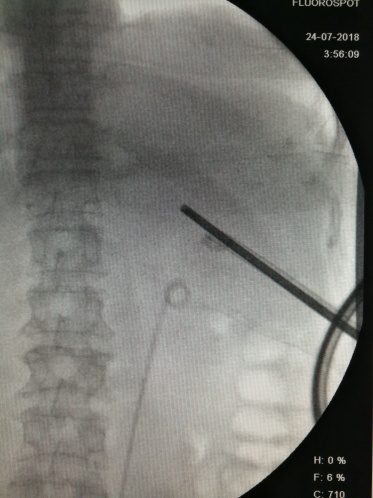

2、行第二个通道穿刺、结合原通道碎石

3、行第三个通道穿刺、碎石

4、极力寻找最后一部分结石

5、最后一个通道穿刺碎石,完全取尽结石

X线定位下穿刺 碎石

据医生术后计算,整个手术在X光机下曝光203次,可谓是在“光合作用”下完成了整个手术操作。另外,该手术有些结石角度大,主刀无法启动碎石器,由主刀固定手术视野,助手启动碎石器,四个医生完美配合下完成了整台手术。